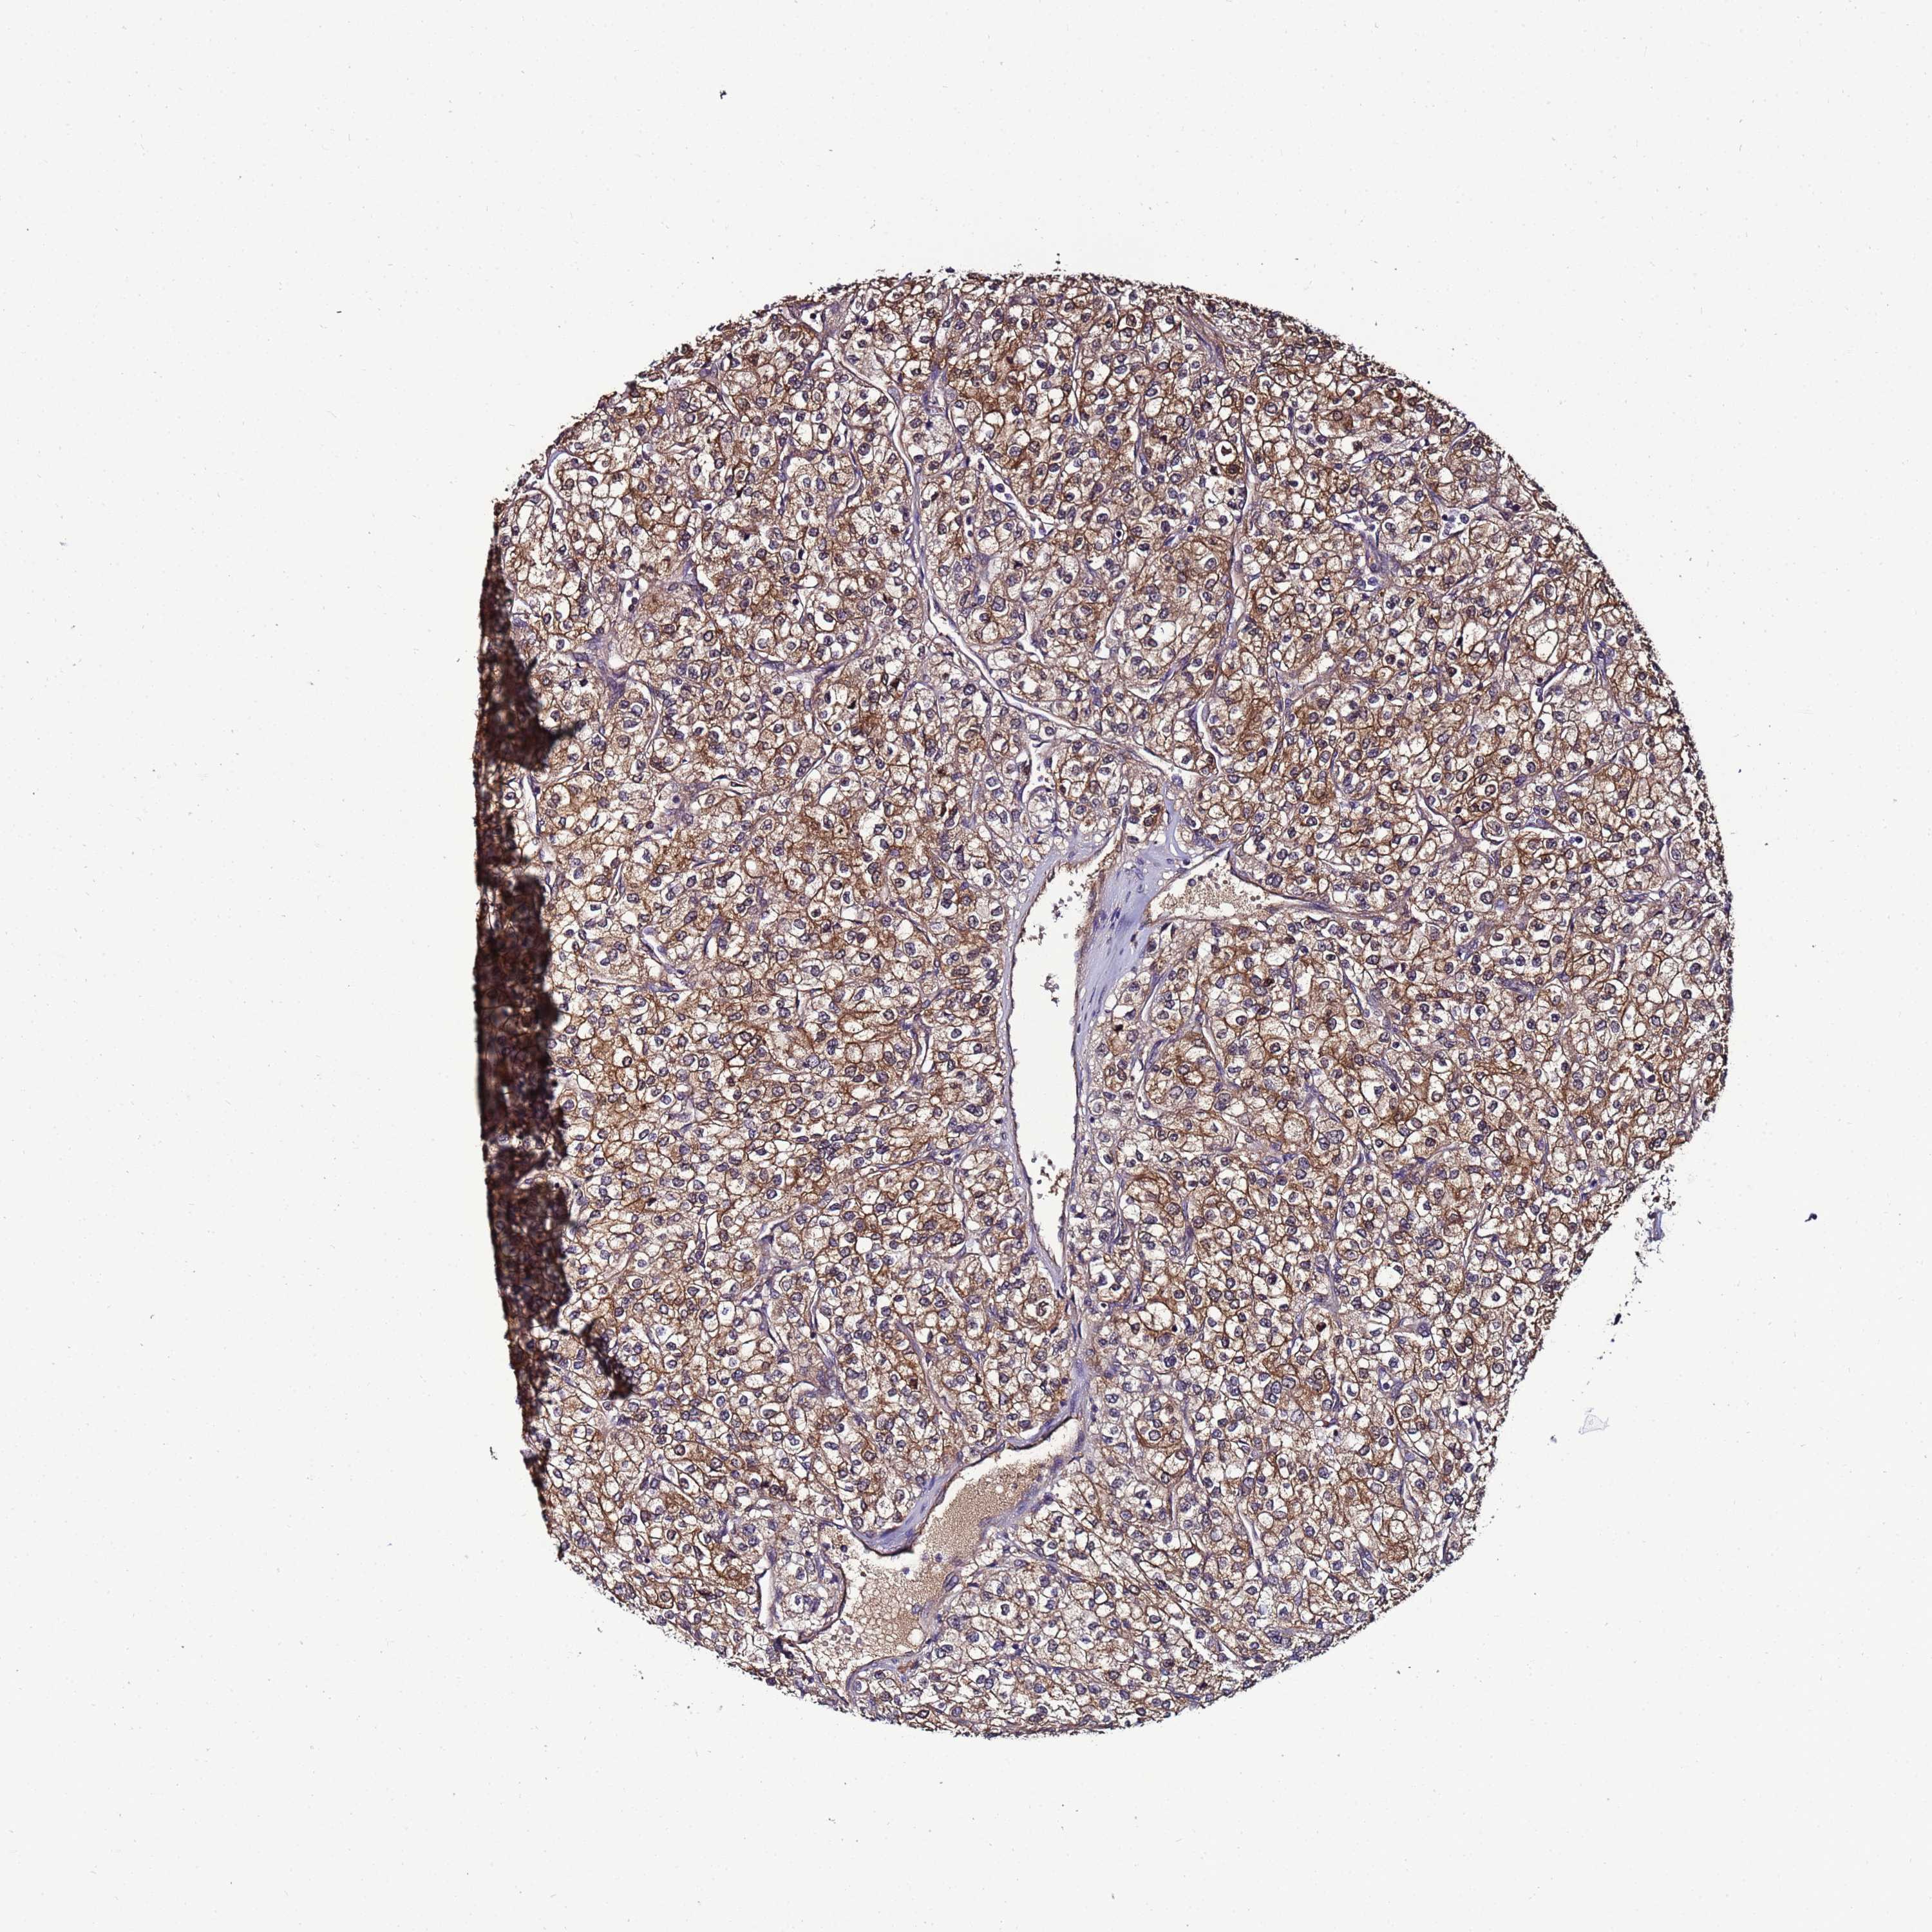

TCGA RNA samplesi

RNA-seq data is reported as average FPKM (number Fragments Per Kilobase of exon per Million reads), generated by the The Cancer Genome Atlas (TCGA) .

Normal distribution across the dataset is visualized with box plots, shown as median and 25th and 75th percentiles. Points are displayed as outliers if they are above or below 1.5 times the interquartile range. FPKM values of the individual samples are presented next to the box plot.

Average pTPM 77.0

Number of samples 521